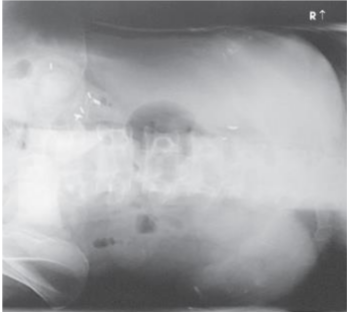

Supine Abdomen (KUB)

CR for an AP abdomen supine enters at the level of

the iliac crests

Breathing instructions for AP abdomen supine

suspend at end of expiration

is the pubic symphysis seen in an ap abdomen supine

Yes